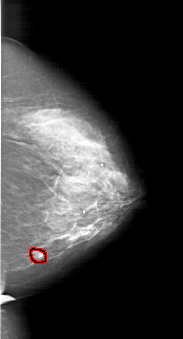

FILE: A_1218_1.RIGHT_MLO.OVERLAY

TOTAL_ABNORMALITIES 1

ABNORMALITY 1

LESION_TYPE MASS SHAPE LOBULATED MARGINS ILL_DEFINED

ASSESSMENT 4

SUBTLETY 2

PATHOLOGY MALIGNANT

TOTAL_OUTLINES 1

BOUNDARY

RIGHT_MLO LINES 6076 PIXELS_PER_LINE 3436 BITS_PER_PIXEL 12 RESOLUTION 43.5 OVERLAY